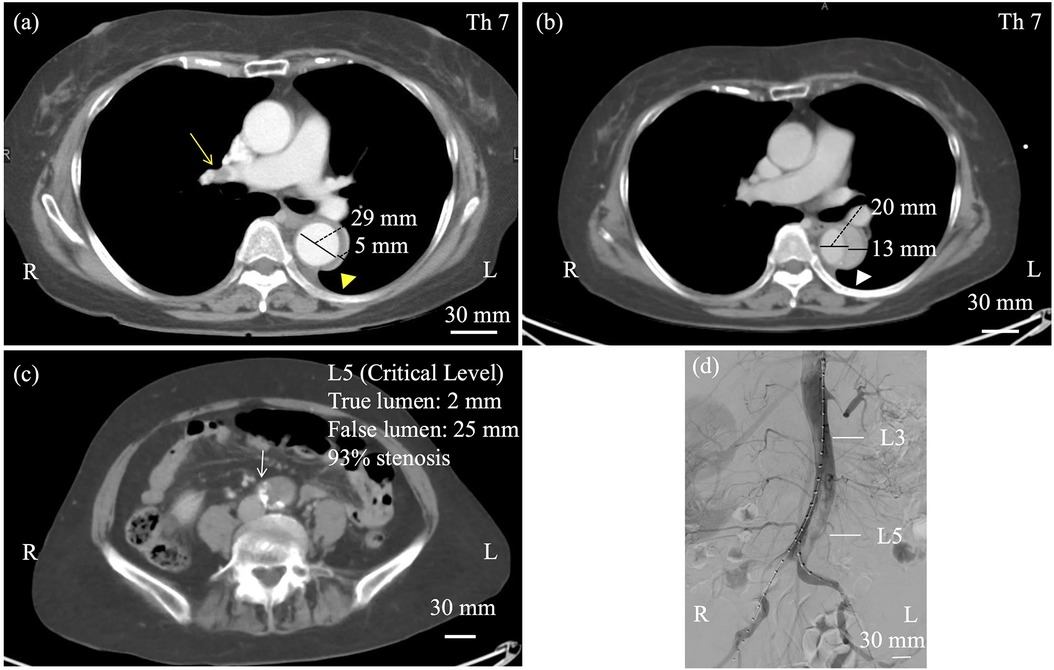

We report a rare, life-saving endovascular intervention in a patient with acute type B aortic dissection (TBAD) complicated by severe lower limb ischemia due to dynamic obstruction. A 67-year-old woman, previously diagnosed with uncomplicated Stanford type B dissection with a thrombosed false lumen, suddenly developed bilateral leg pain and absent distal pulses on day 12. CT revealed a new entry tear in the descending aorta, leading to false lumen reperfusion and collapse of the true lumen at the abdominal aorta and both common iliac arteries. As appropriate thoracic endovascular aortic repair and endovascular aortic repair devices were not immediately available, emergency repair was performed using four self-expanding bare-metal stents via bilateral femoral access. This achieved prompt true lumen re-expansion and restoration of distal pulses. Post-procedure imaging confirmed improved perfusion. Although extra-anatomical bypass is often considered, complete collapse of the abdominal true lumen made it unlikely to be effective. This case demonstrates that widely available bare-metal stents offer a practical and effective emergency option for restoring distal perfusion when standard devices are not accessible. Importantly, this approach should be regarded as palliative for limb salvage rather than definitive treatment of the entry tear.